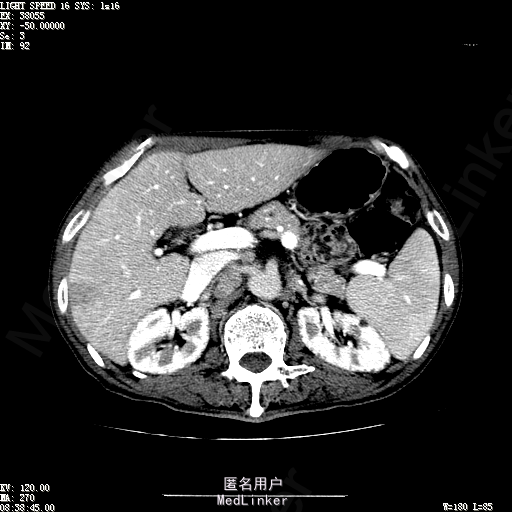

查体:体温36.3℃,脉搏76次/分,呼吸18次/分,血压120/80mmHg。神志清晰,肝病面容,皮肤粘膜颜色正常无黄染,全身皮肤未见皮疹、瘀点及紫癜,肝掌阳性,未见蜘蛛痣,浅表淋巴结未触及。巩膜无黄染,结膜正常。双肺呼吸音清,无胸膜摩擦音。心率:76次/分,心律齐,心音正常,无杂音,无心包摩擦音。腹平坦,无腹壁静脉曲张,未见胃肠型及蠕动波,双侧腹股沟可见手术瘢痕,脐部正常。触诊:无压及痛反跳痛,无腹肌紧张,无腹部包块。肝脾肋下未触及,Murphy征阴性,肾未触及,移动性浊音阴性。肝肾区叩击痛阴性,无脾区叩击痛。听诊:肠鸣音正常,4次/分,无气过水声。脊柱无侧弯,脊柱活动度正常,棘突正常,四肢正常,关节正常,无下肢水肿,无下肢静脉曲张,无杵状指趾。扑翼样震颤阴性。 门诊化验ALT9U/L,AST21U/L,HBVDNA<1.0E+03IU/mL,HBsAg1138IU/mL,WBC6.2x10^9/L,RBC3.92x10^12/L,PLT167x10^9/L,AFP28.95ng/ml,AFU 29U/L,彩超示肝右叶肝回声,大小约5.1*3.5cm,Fibroscan:脂肪变:163硬度10.8。 CT如下图

诊断:1、乙肝肝硬化 活动性 代偿期 原发性肝癌 2、胃溃疡 3、十二指肠球部溃疡 处理:血管介入治疗:手术者术前查看患者相关情况:化验回报:血细胞分析(五分类):*白细胞计数 8.1 10^9/L、*红细胞计数 4.00 10^12/L↓、*血小板计数 202.0 10^9/L、*血红蛋白 136 g/L,肝功酶谱:*丙氨酸氨基转移酶 5 U/L、天门冬氨酸氨基转移酶 22 U/L、*白蛋白 37.6 g/L、*总胆红素 17.8 umol/L,肾功能检测:*尿素 5.79 mmol/L、*肌酐 67.1 umol/L,凝血五项:凝血酶原时间 10.7 秒↓、凝血酶原百分活动度 93.3 %,甲胎蛋白测定:甲胎蛋白 30.30 ng/mL↑。患者病情平稳,今日术前准备,签署相关文件。 手术简要经过:患者平卧位,以右侧腹股沟区为中心常规消毒、铺巾、利多卡因局麻。改良Seldinger法逆行穿刺右侧股动脉成功,置入5F血管鞘。经血管鞘造影,见髂外动脉明显迂曲,经鞘送入超滑导丝,退出原5F血管鞘,换入5F长25厘米血管鞘。沿导丝送入肝管,将管头送入腹腔干,进一步送至肝右动脉。经正位、右前斜30°造影,明确肝右叶膈顶一处较大肿瘤染色,S5段一处较小肿瘤染色。以微导管超选S6段肝动脉干,经多角度造影明确为肿瘤供血动脉,注入混悬液(碘化油10毫升+雷替曲塞2毫克)3毫升,明胶海绵颗粒1/12支。再以微导管超选S7段肝动脉干,造影明确为肿瘤供血动脉,注入混悬液2毫升,明胶海绵颗粒1/20支。再以微导管超选S8段分支,造影明确为肿瘤供血动脉,注入混悬液2.8毫升,明胶海绵颗粒1/12支。再以微导管超选S5段肝动脉分支,造影明确为较小肿瘤供血动脉,注入混悬液0.8毫升,明胶海绵颗粒1/30支。退出微导管。经肝右动脉注入奥沙利铂100毫克。退出肝管。拔出血管鞘,局部压迫5分钟。加压包扎。